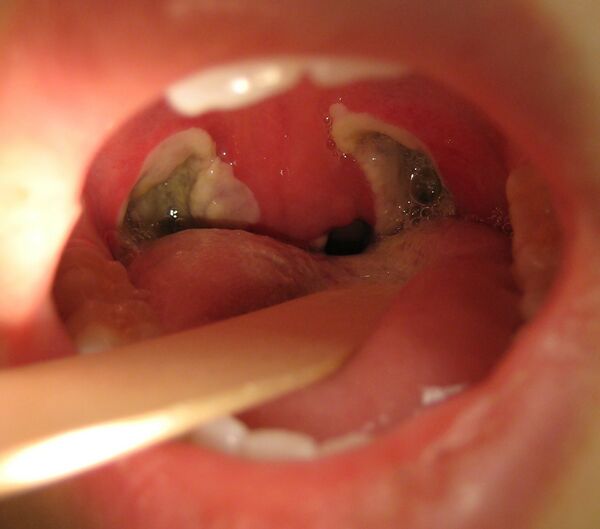

Тонзиллэктомия

Тонзиллэктоми́я (от лат. tonsilla — миндалевидная железа и греч. εκτομή — иссечение, удаление) — известная более 3000 лет хирургическая операция по полному удалению нёбных миндалин вместе с соединительно-тканной капсулой[1]. Выполняется при рецидивах острого тонзиллита или аденоидита, носовых обструкциях дыхательных путей, апноэ, храпе и паратонзиллярном абсцессе. До настоящего времени остаётся одним из наиболее распространённых оперативных вмешательств.

Галерея